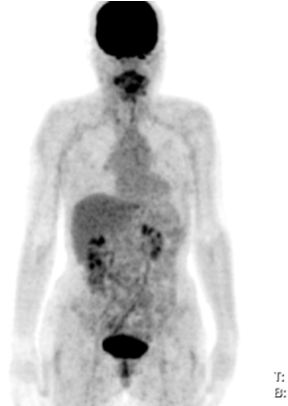

Mô phỏng tốt nhất trên PET/CT với hệ thống laser định vị 3 chiều. Vì PET/CT ghi hình dựa trên sự tập trung cao thuốc phóng xạ FDG vào các tế bào ung thư, cho hình ảnh chuyển hóa của khối u, sớm, chính xác hơn hình ảnh giải phẫu của CT đơn thuần (hình 1), xác định được mức độ xâm lấn của u cũng như phát hiện những di căn hạch kể cả với kích thước nhỏ ở mức độ phân tử, mức độ tế bào từ đó cho phép xác định thể tích xạ trị cũng như việc lập kế hoạch xạ trị được triệt để nhất (hình 2). Khi chụp mô phỏng: bệnh nhân trong tư thế nằm ngửa, cổ ưỡn sao cho đường thẳng giữa cằm - xương chũm vuông góc với mặt bàn; đầu bệnh nhân được giữ cố định bằng mặt nạ, tổng hợp từ loại chất dẻo đặc biệt.

Hình ảnh CT mô phỏng khó xác định được vị trí khối u

Hình ảnh PET/CT mô phỏng thấy rõ khối u vòm

Hình 1: Hình CT và PET/CT mô phỏng ung thư vòm.